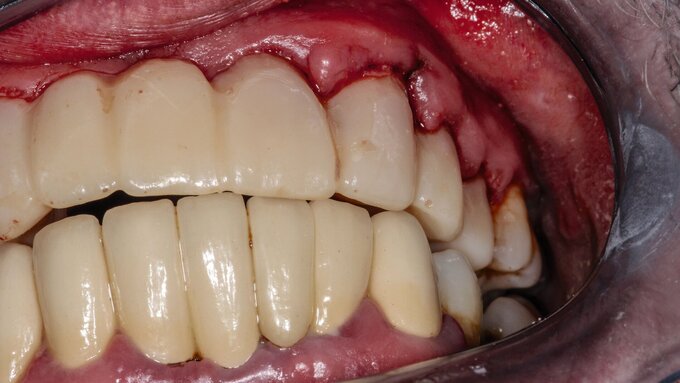

Anhand von In-vitro- und In-vivo-Modellen konnten die Forschenden nachweisen, dass die Blockierung von CD47 oder TSP-1 die Immunabwehr gegen das Bakterium deutlich verbessert. Mäuse ohne CD47 zeigten eine erhöhte Fähigkeit, P. gingivalis zu eliminieren – ein Hinweis darauf, dass die gezielte Beeinflussung dieses Signalwegs eine vielversprechende therapeutische Strategie zur Behandlung von Parodontalerkrankungen sein könnte.

„Die derzeitigen Parodontalbehandlungen konzentrieren sich auf die mechanische Reduzierung der bakteriellen Belastung, aber wenn man versteht, wie diese Bakterien der Immunantwort entgehen, eröffnen sich neue therapeutische Möglichkeiten“, fügte Nussbaum hinzu. „Die gezielte Beeinflussung der CD47-TLR2-Signalübertragung oder von TSP-1 könnte ein neuer Ansatz zur Behandlung chronischer Infektionen im Zusammenhang mit der oralen und systemischen Gesundheit sein.“

Angesichts des engen Zusammenhangs zwischen Parodontitis und Herz-Kreislauf-Erkrankungen sowie neurodegenerativen Störungen hätte diese Entdeckung weitreichende Auswirkungen über die Zahnmedizin hinaus. Künftige Forschung soll nun untersuchen, wie diese Erkenntnisse in klinische Therapien umgesetzt werden können, um die Immunantwort auf chronische bakterielle Infektionen gezielt zu verbessern.